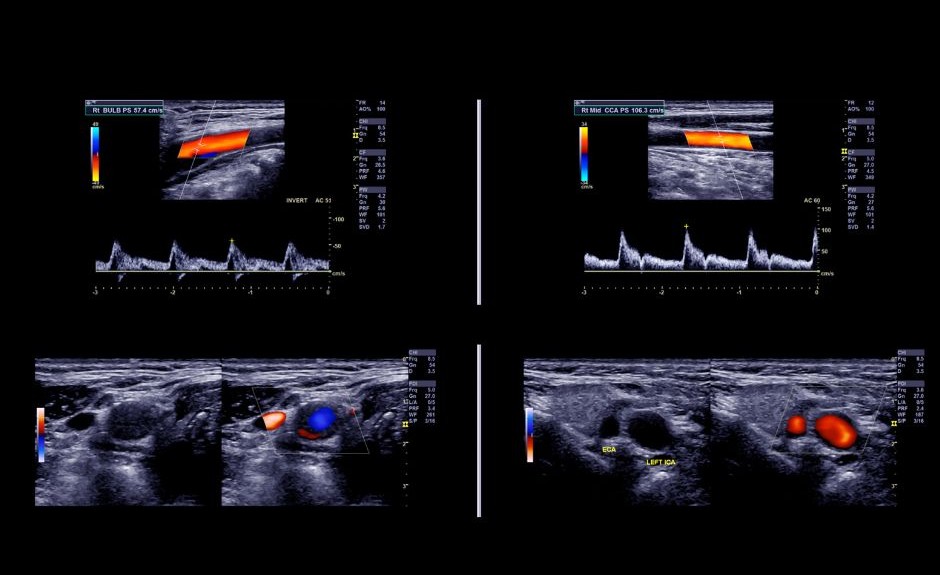

USG Doppler – bezpieczne badanie naczyń mózgowych i szyjnych

USG Doppler to jedno z najważniejszych badań w diagnostyce chorób naczyniowych układu nerwowego. Pozwala ocenić, czy przepływ krwi w tętnicach i żyłach jest prawidłowy, a tym samym – czy mózg otrzymuje odpowiednią ilość tlenu i substancji odżywczych. Badanie to jest nieinwazyjne, bezbolesne i całkowicie bezpieczne, dlatego może być wykonywane nawet u osób starszych oraz pacjentów z chorobami przewlekłymi.

Pacjent leży wygodnie na kozetce, a lekarz przykłada do skóry głowicę aparatu USG, przesuwając ją wzdłuż szyi lub – w przypadku badania przezczaszkowego – po określonych punktach głowy.

Na monitorze widoczny jest obraz naczyń krwionośnych oraz kolorowa wizualizacja przepływu krwi. Cała procedura trwa zwykle 10–20 minut i nie wymaga żadnego przygotowania. Po zakończeniu badania pacjent może natychmiast wrócić do codziennych zajęć.

USG Doppler tętnic szyjnych i kręgowych

Badanie to umożliwia ocenę drożności naczyń doprowadzających krew do mózgu – tętnic szyjnych wspólnych, wewnętrznych, zewnętrznych oraz tętnic kręgowych.

USG Doppler przezczaszkowy

To badanie pozwala na ocenę przepływu krwi w tętnicach wewnątrzczaszkowych, m.in. w tętnicach środkowych, przednich i tylnych mózgu. Wykonywane jest przez cienkie kości czaszki (np. w okolicy skroni lub potylicy), przy użyciu specjalnej głowicy ultrasonograficznej.